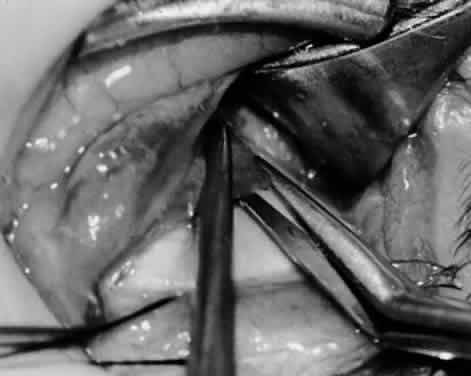

Fig. 21. A hemostat is placed adjacent to the insertion of the right inferior oblique muscle.

Fig. 22. An Aebli scissor is used to section the inferior oblique muscle from the globe.

Fig. 23. The inferior oblique muscle is drawn into the operative field with a hemostat. This step may be used for the recession procedure if the surgeon is concerned about the placement of the 6-0 Vicryl suture while the muscle is attached to the globe in the proximity of the macula. The recession sequence would follow after the placement of the suture while the muscle is grasped in the hemostat.